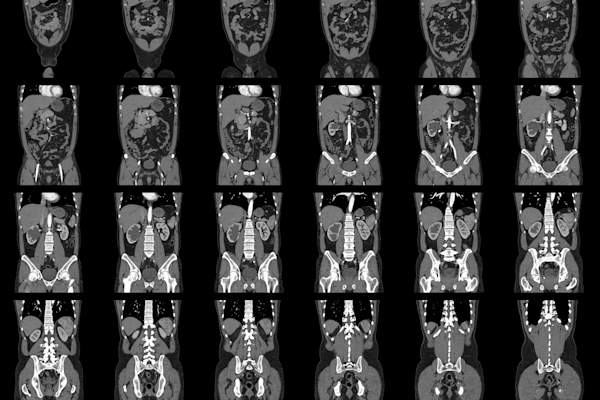

结肠癌并不总是通过BMs发出警告信号。“早期结肠癌可能根本没有任何症状,可能是在结肠镜检查、腹部CAT扫描或其他影像学检查中偶然发现的。或者在标准的血液测试中发现,”Poppers博士说,或者通过专门寻找一种叫做癌胚抗原(CEA)的化学物质的测试,结肠癌可以产生这种物质。这就是为什么45岁开始做结肠镜检查很重要,如果你有家庭病史或炎症性肠病病史,你的风险更高,那就早做。